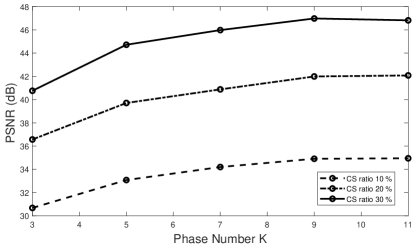

Medical image compressive sensing is an everlasting practical application in image reconstruction area. In this section we test the performance of the proposed ResGD-Net on compressive sensing reconstruction of brain MR images [3] (CS-MRI). In CS-MRI problem, the data fidelity term is , where , is a binary selection matrix representating the sampling trajectory, and is the discrete Fourier transform. We randomly pick images from the brain MRI datasets [3], then crop and keep the central part with less background. Then we at random divide the dataset to images for training and for testing. Among this section, we present the comparison results between ResGD-Net and ISTA-Net+ [33], where the latter one is a state-of-the-art method in tackling with CS-MRI problem. For fairness, both algorithms compared here are evaluated on the same dataset and metrics. Experiments are conducted across different sampling ratios , and of to show the generality. The study of ResGD-Net on different sampling ratios and various phase numbers is shown in Fig. 4. The PSNR comparison with ISTA-Net+ is shown in Table. 2. The result enhancement of the proposed ResGD-Net against ISTA-Net+ is remarkable across all sampling ratios even though we only use approximately many number of parameters than ISTA-Net+ [33].